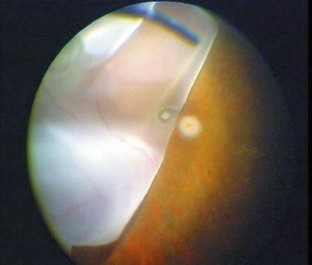

A 78-year-old woman with AFVD underwent MT with 360° retinotomy 3–4 months after loss of reading ability. Most of the vitelliform material was lost during surgery; the subfoveal tissue was excised, fixed in aldehydes, postfixed in reduced OsO4 and embedded in epoxy resin. Semithin sections were stained with toluidine blue for light microscopy (LM) and thin sections with uranyl acetate and lead citrate for transmission electron microscopy (TEM).

Results

Postoperatively, the patient developed a retinal detachment complicated by proliferative vitreoretinopathy (PVR) requiring two additional vitreoretinal procedures before finally the silicone oil could be removed. Twenty-two months after MT the distance visual acuity was unchanged at 0.2; the near visual acuity had improved from less than 0.1 before MT to 0.4. The retina was completely attached. LM and TEM revealed serious alterations indicative of a breakdown of the outer layer of the retina.